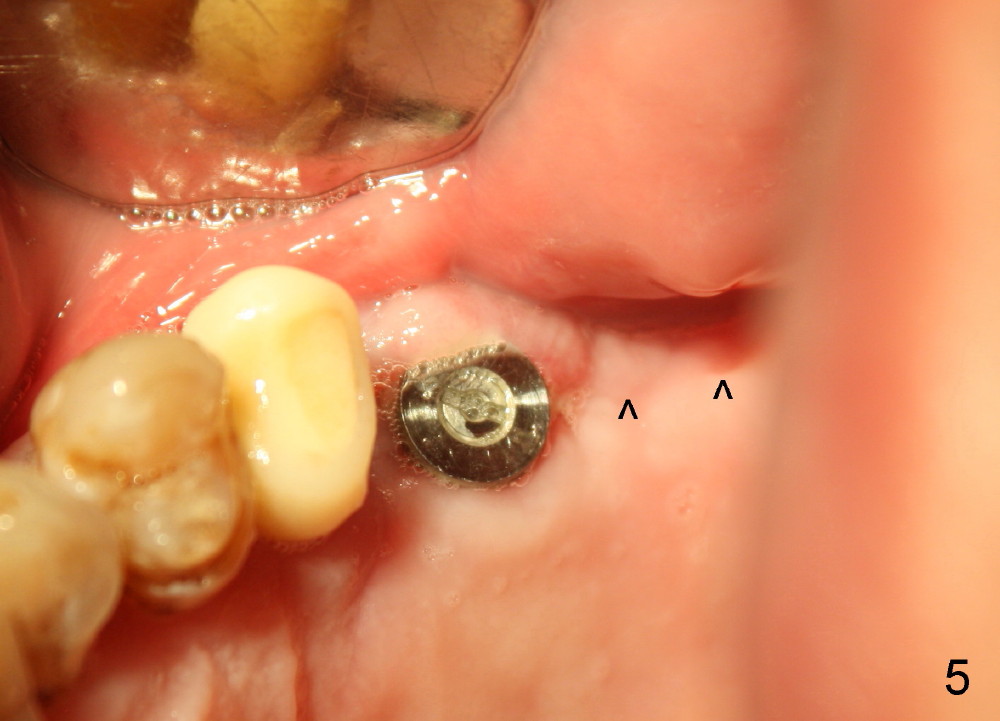

Although there is swelling 1-2 days postop, the wound is healing 8 days postop (Fig.5,6).

Bone graft remains in place 2 months postop (Fig.7 arrowheads); its density increses 4 months postop (Fig.8). The gingiva around the implant and abutment at the site of #14 is healthy (Fig.9 (4 months postop before final impression);10 (5 months postop immediately before final cementation)).